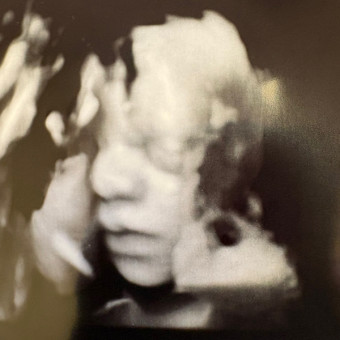

Baby L's Registry

Jacqueline & Darren Labenberg

We can't wait to celebrate Baby L with you!